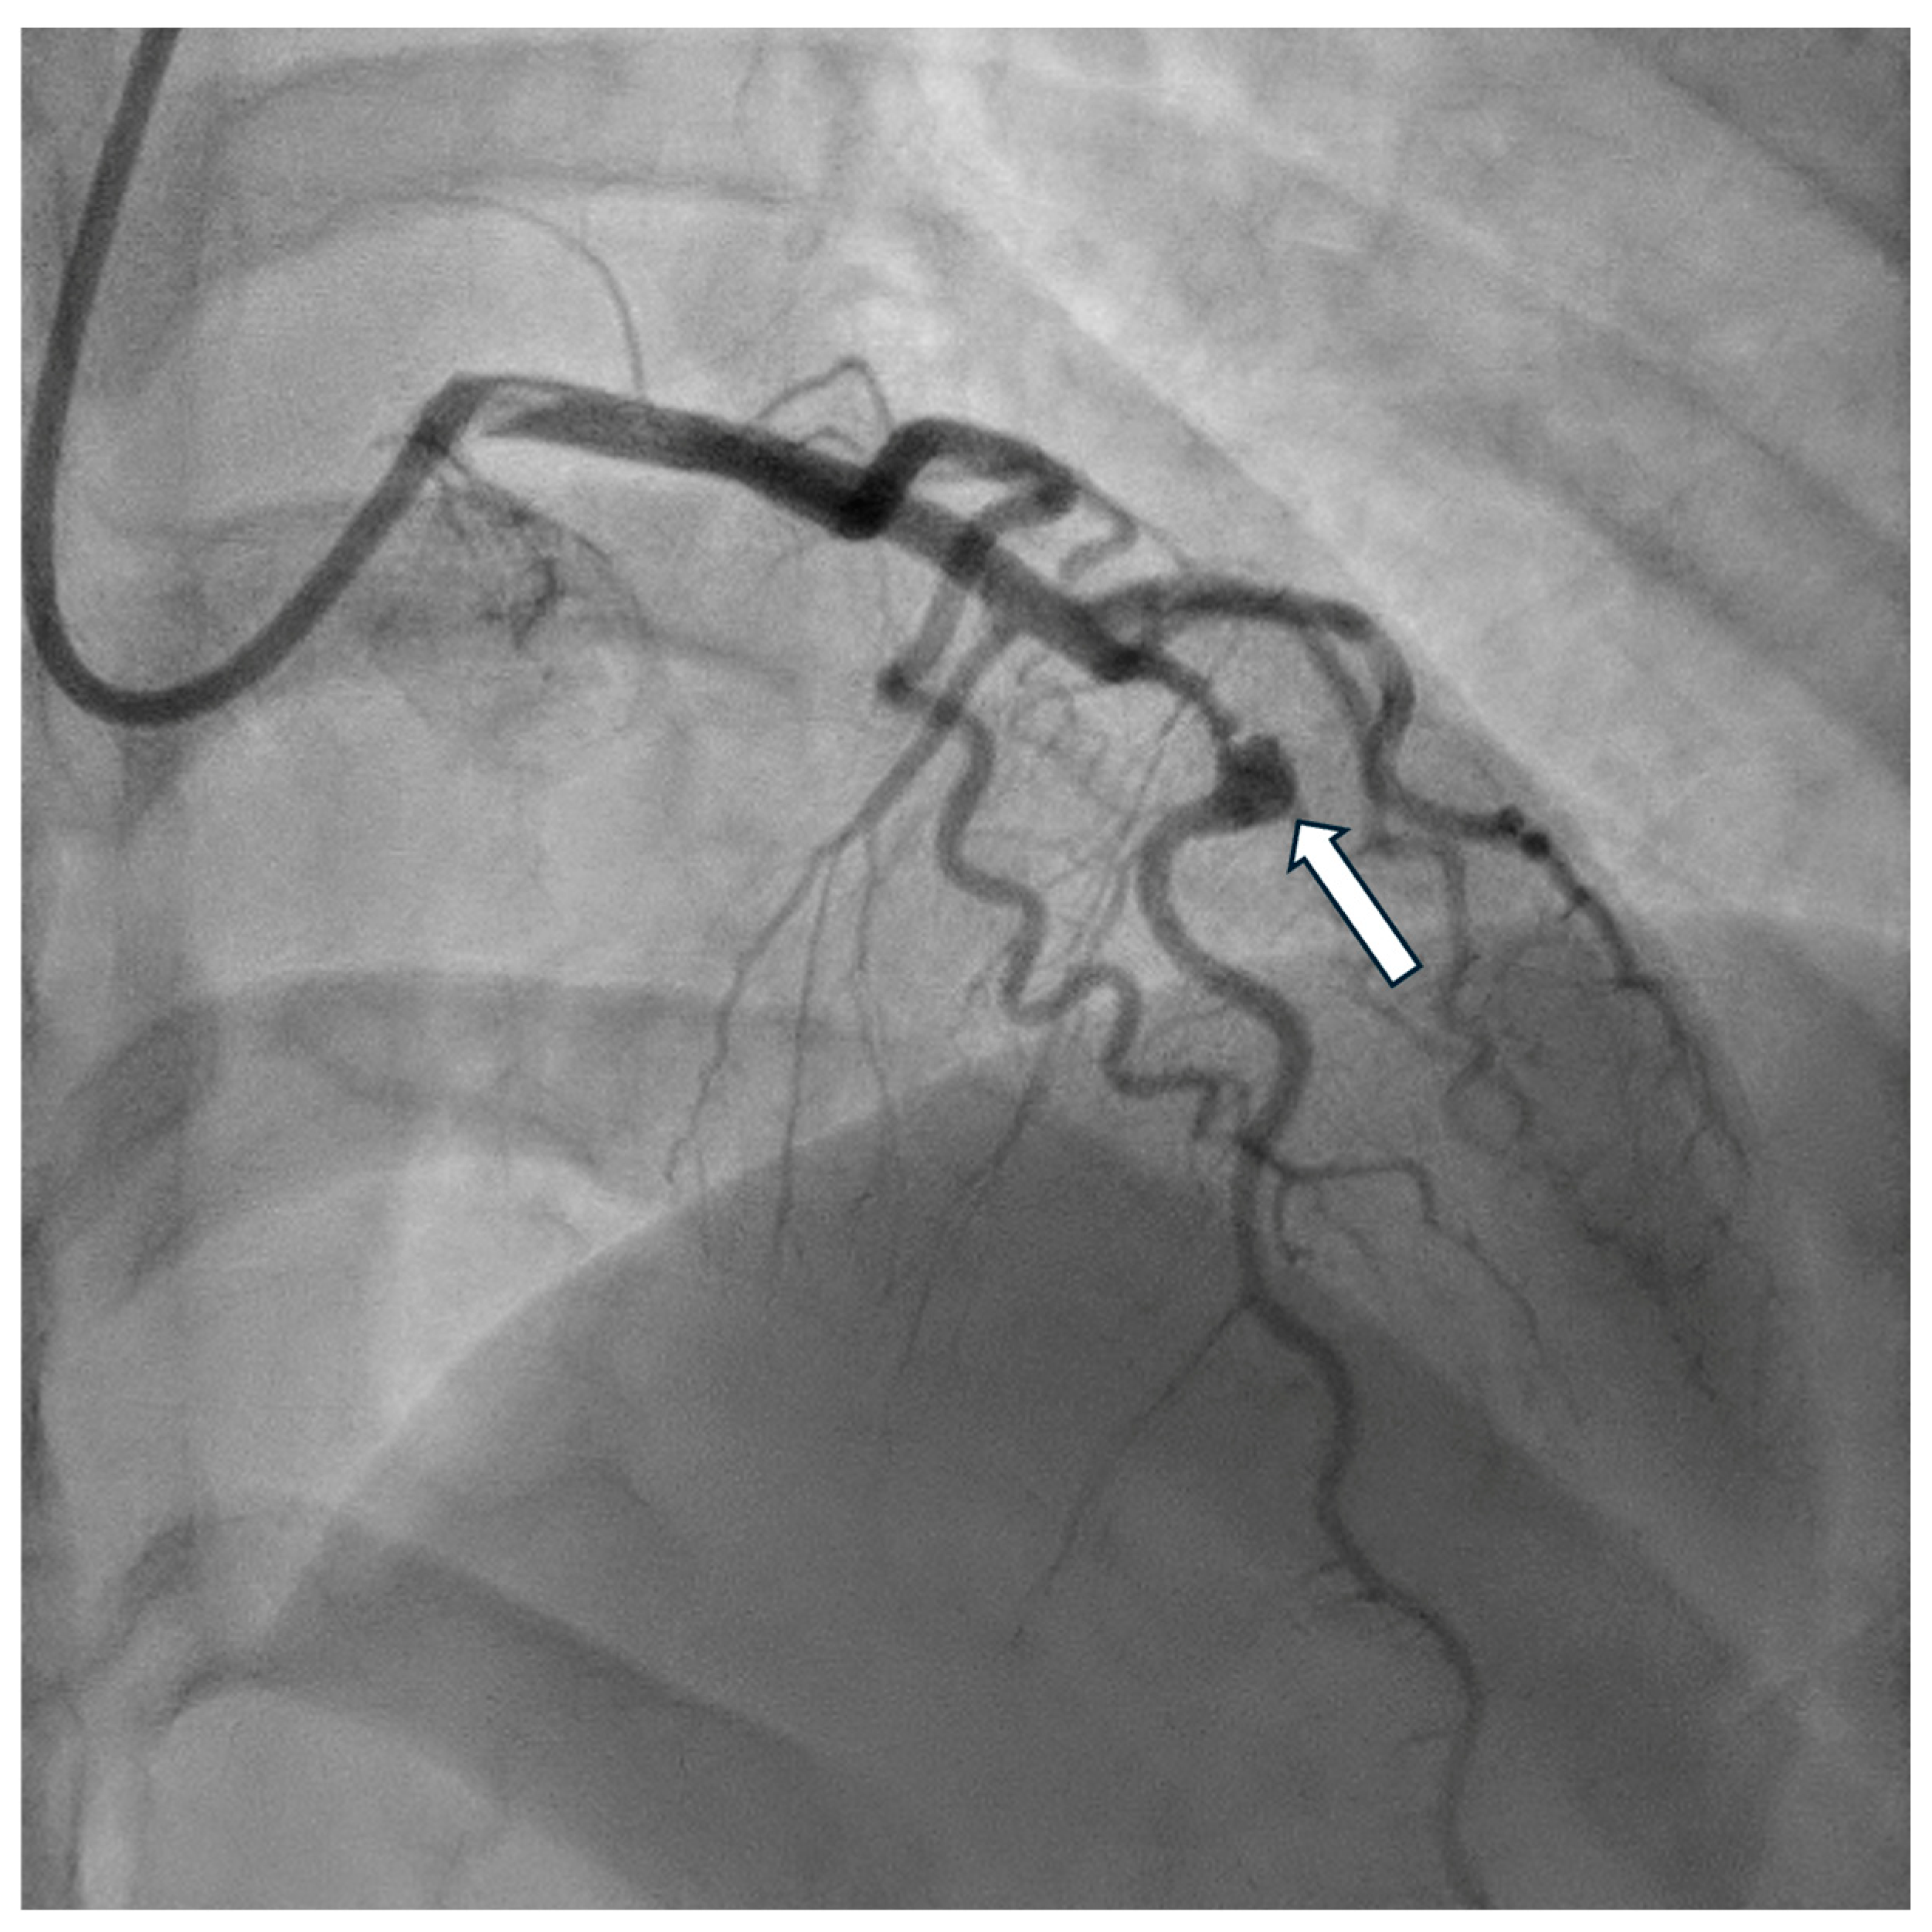

- Papadakis, M.C.; Manginas, A.; Cotileas, P.; Demopoulos, V.; Voudris, V.; Pavlides, G.; Foussas, S.G.; Cokkinos, D.V. Documentation of slow coronary flow by the TIMI frame count in patients with coronary ectasia. Am. J. Cardiol. 2001, 88, 1030–1032. [Google Scholar] [CrossRef] [PubMed]

- Gulec, S.; Atmaca, Y.; Kilickap, M.; Akyürek, O.; Aras, O.; Oral, D. Angiographic assessment of myocardial perfusion in patients with isolated coronary artery ectasia. Am. J. Cardiol. 2003, 91, 996–999. [Google Scholar] [CrossRef]

- Akyürek, Ö.; Berkalp, B.; Sayın, T.; Kumbasar, D.; Kervancıoğlu, C.; Oral, D. Altered coronary flow properties in diffuse coronary artery ectasia. Am. Heart J. 2003, 145, 66–72. [Google Scholar] [CrossRef]